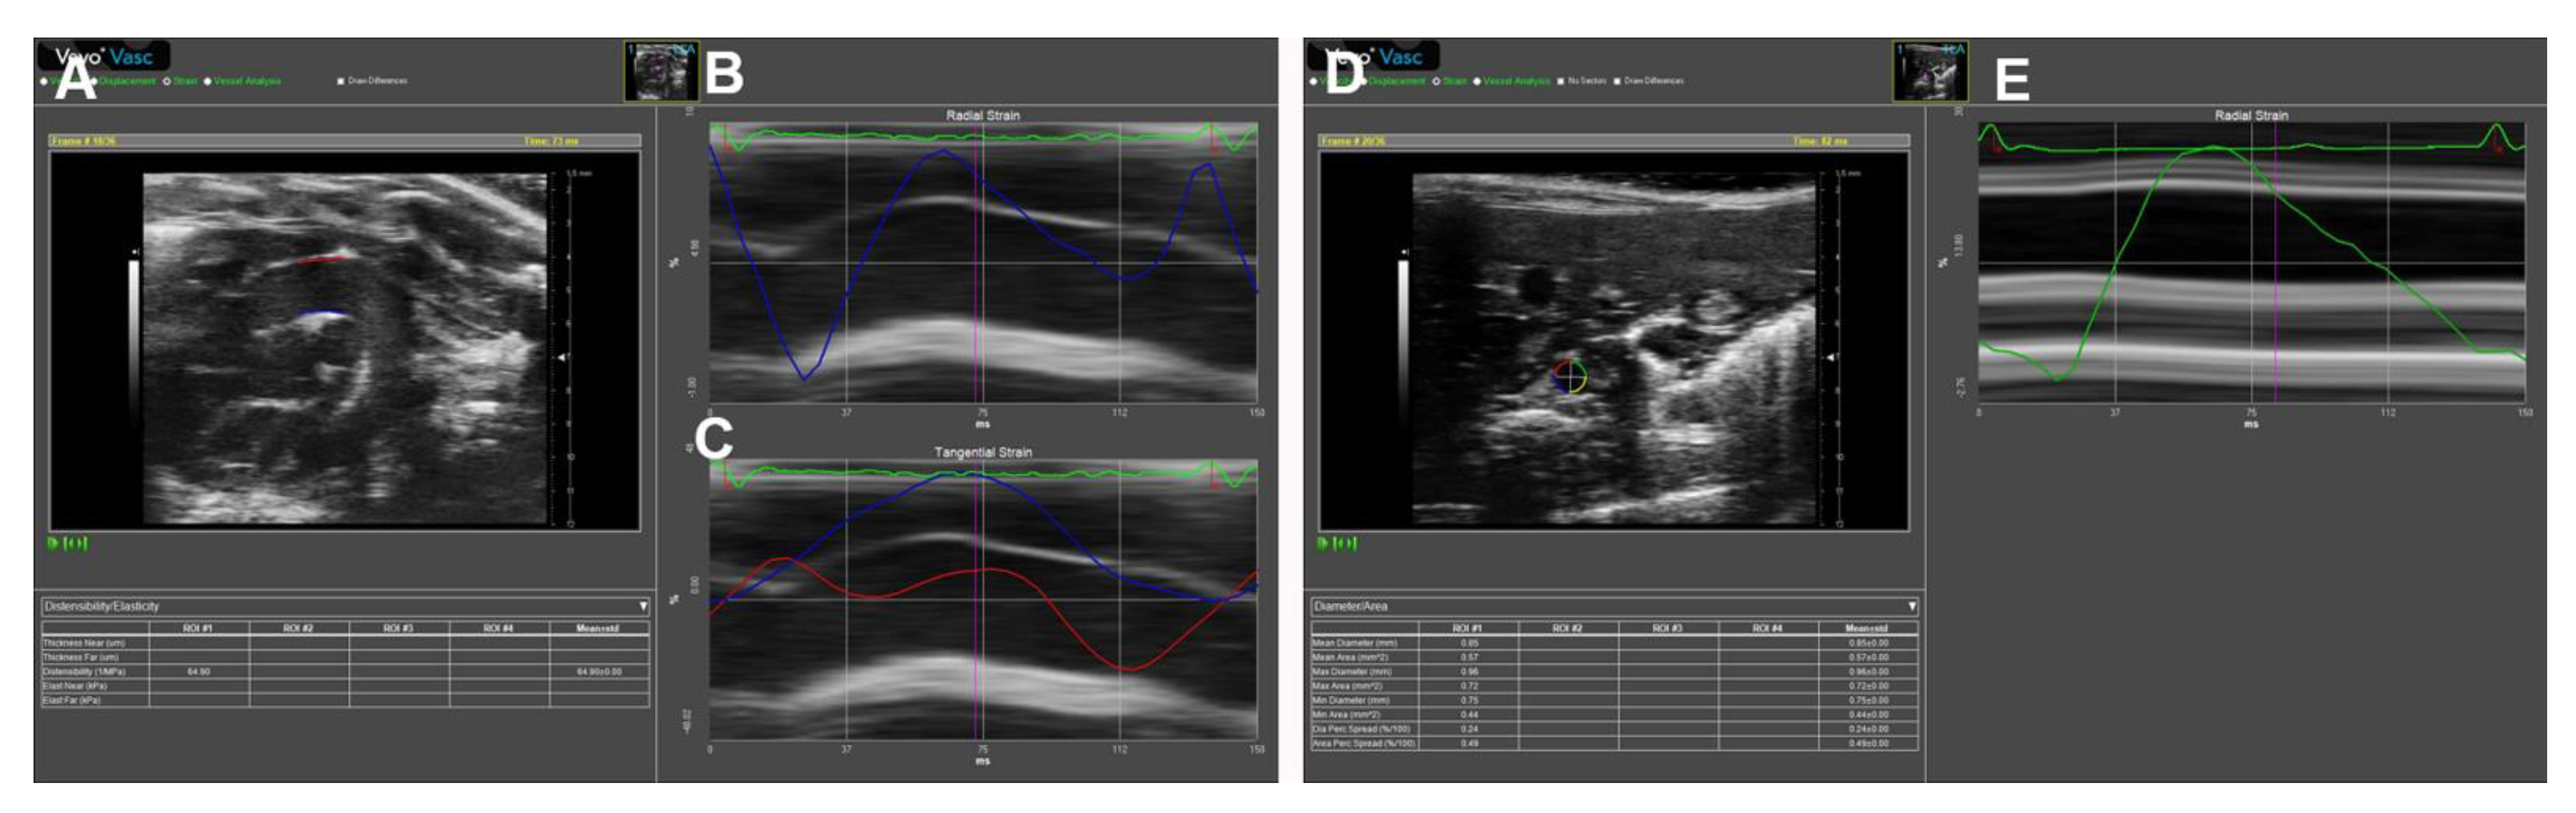

STI is another newly developed ultrasonographic method used to quantify the tissue wall’s deformation of subsurface structures with high spatial resolution. The speckle pattern can be tracked consecutively from frame to frame and ultimately resolved into angle-independent 2D and three-dimensional (3D) strain-based sequences, providing both quantitative and qualitative information regarding tissue deformation and motion. So far, speckle tracking using in-vessel deformation has been limited to 2D-STI, while the application of 3D-STI in vessels is still undergoing technological developments. 2D-STI can be obtained by B-mode, and the corresponding circumferential strain rate can be calculated by using the dedicated software. Based on frame-by-frame tracking of tiny echo-dense speckles within the tissue, 2D-STI enables the calculations of motion and deformation variables, such as velocity, displacement, strain, and strain rate, through the assessment of the tissues’ lengthening and shortening [43,61]. As illustrated in the upper panel of Figure 9, with a 2D ultrasonographic image of the human aorta, a line was manually drawn along the inner side of the DAAo circumference, and the additional lines within a 15-mm-wide region of interest would be automatically generated by the software (Automated Cardiac Motion Quantificationᴬ⋅ᴵ, Qlab 13.0; Philips Healthcare, Amsterdam, The Netherlands). The shape and width of the regions of interest could be manually adjusted. A cine loop preview feature allowed visual confirmation that the internal line followed the vascular expansion and recoil movements throughout the cardiac cycle. Based on these measurements, the circumferential strain rate can be automatically or semi-automatically calculated by the software, as shown in the lower panel of Figure 9.

Due to its high feasibility and excellent reproducibility, this technique may be of particular benefit in small animal imaging. Recently, we have used 2D-STI to obtain mouse AS. As shown in Figure 10A–E, the images of the parasternal long-axis of AAo and subcostal views of DAAo were successfully obtained by B-mode imaging using a VisualSonics Vevo 3100 system (FUJIFILM VisualSonics Inc., Toronto, ON, Canada). The data were analyzed by using the Vevo Vasc software (Vevo LAB 3.2.6), including the diameter, area, strain, distensibility/elasticity, and wall thickness.

Figure 10. Representative images of mouse aortic assessments by 2D speckle tracking. Images acquired from a four-month-old C57BL/6J mouse over one cardiac cycle. (A): B-mode image of the ascending aorta (AAo) in long-axis orientation. (B): Regional radial strain curve superimposed M-mode image of the aorta. (C): Tangential strain curve superimposed M-mode image of the aorta. (D): A B-mode image of the descending abdominal aorta (DAAo) in short-axis orientation. (E): Regional radial strain curve superimposed M-mode image of the aorta.